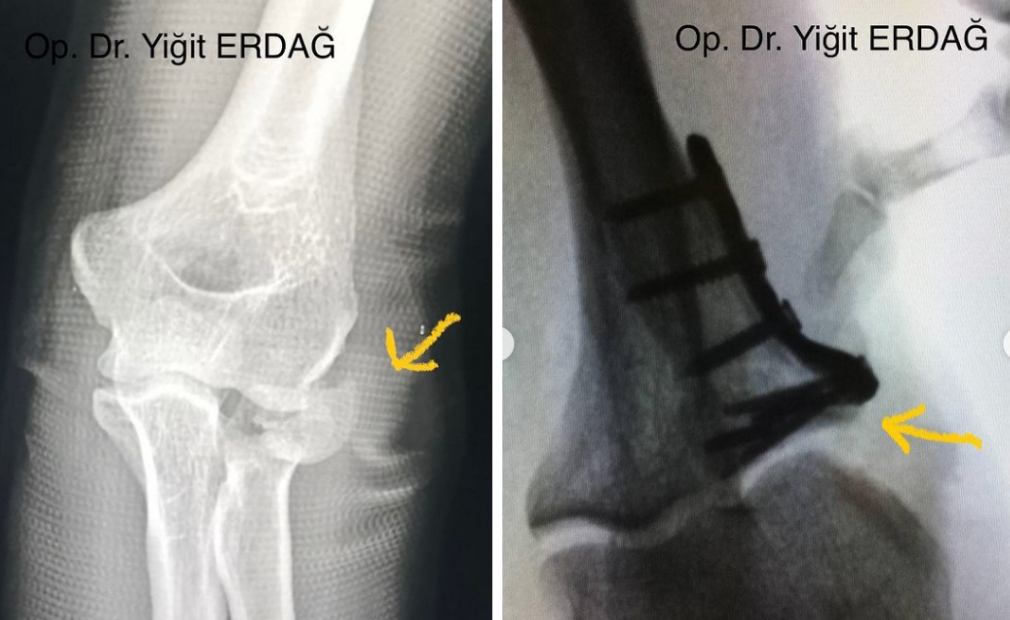

- Dirsek Cerrahisi

Kaza, yaralanma gibi durumlar sonucu oluşan kemik ve eklemlerde meydana gelen kırıklar, çıkıklar cerrahi olarak tedavi edilebilir.

Omuz, el bileği, parmak, kalça, dirsek, diz, ayak bileği gibi eklemlerde yaşanan sorunlar kapalı cerrahiyle (artroskopi) tedavi edilebilir.